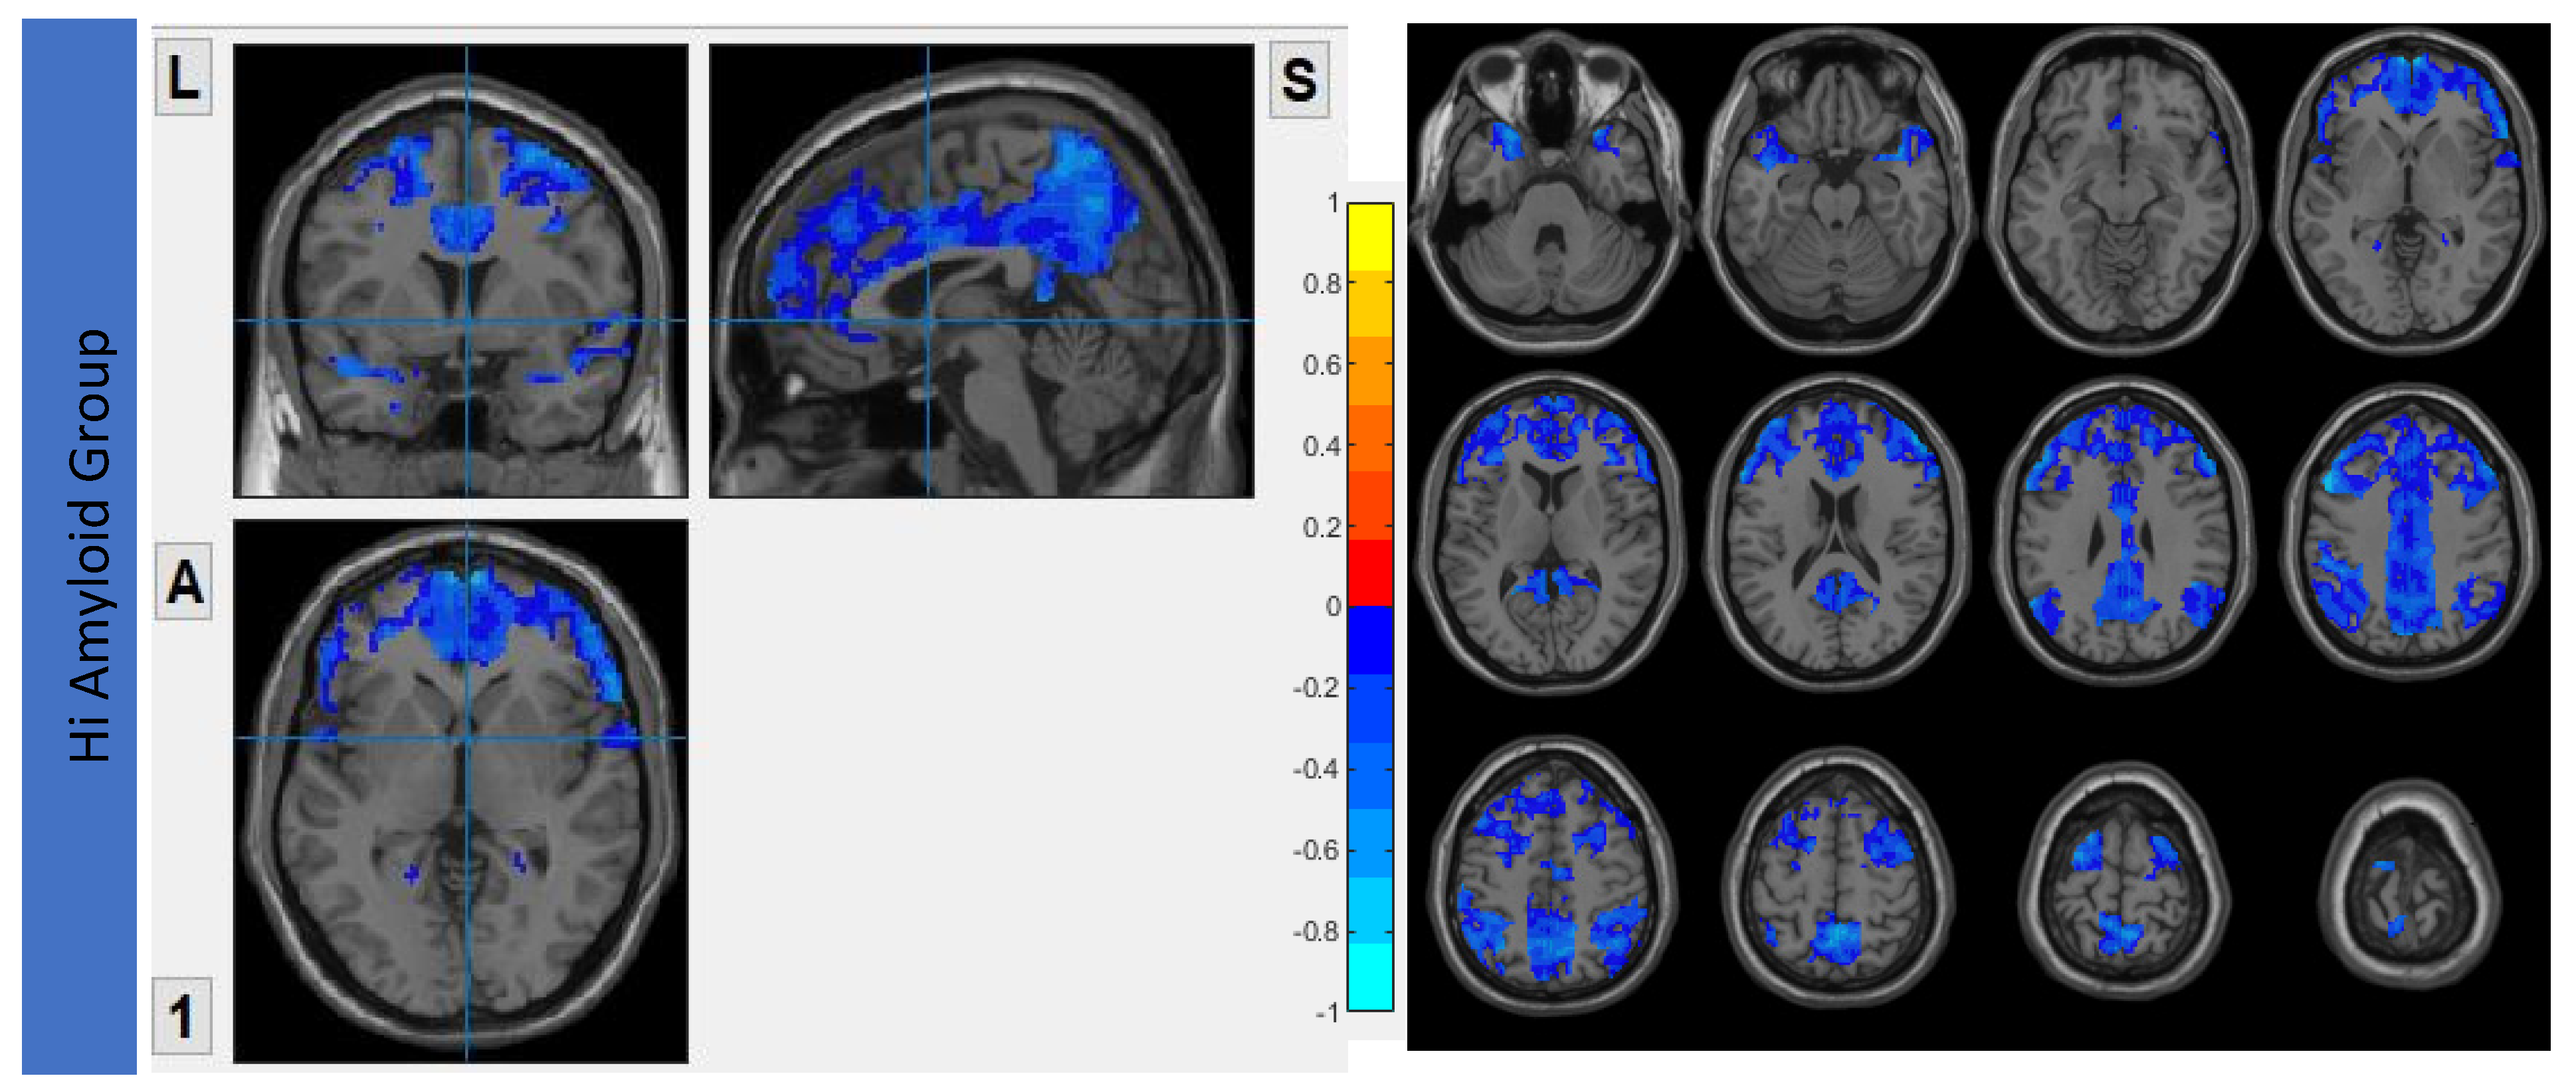

7.2. Within CEN

In the HiAmy group, voxel-wise correlation analysis showed negative correlation (r = −0.134 to −0.545, p < 0.05) in the correlation map, indicating the Aβ accumulation relates to the reduction of functional connectivity of that region. However, in the LowAmy group, voxel-wise correlation analysis showed positive correlation (r = 0.225 to 0.628, p < 0.05) in the correlation map, indicating the Aβ accumulation relates to the increased functional connectivity of that region. Details were shown in Figure 4.

Figure 4.

Correlation between Aβ burden and IFC in CEN.